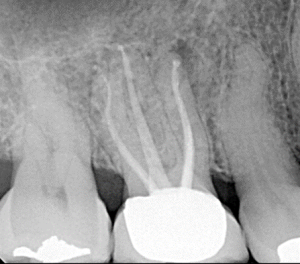

Clinical Cases